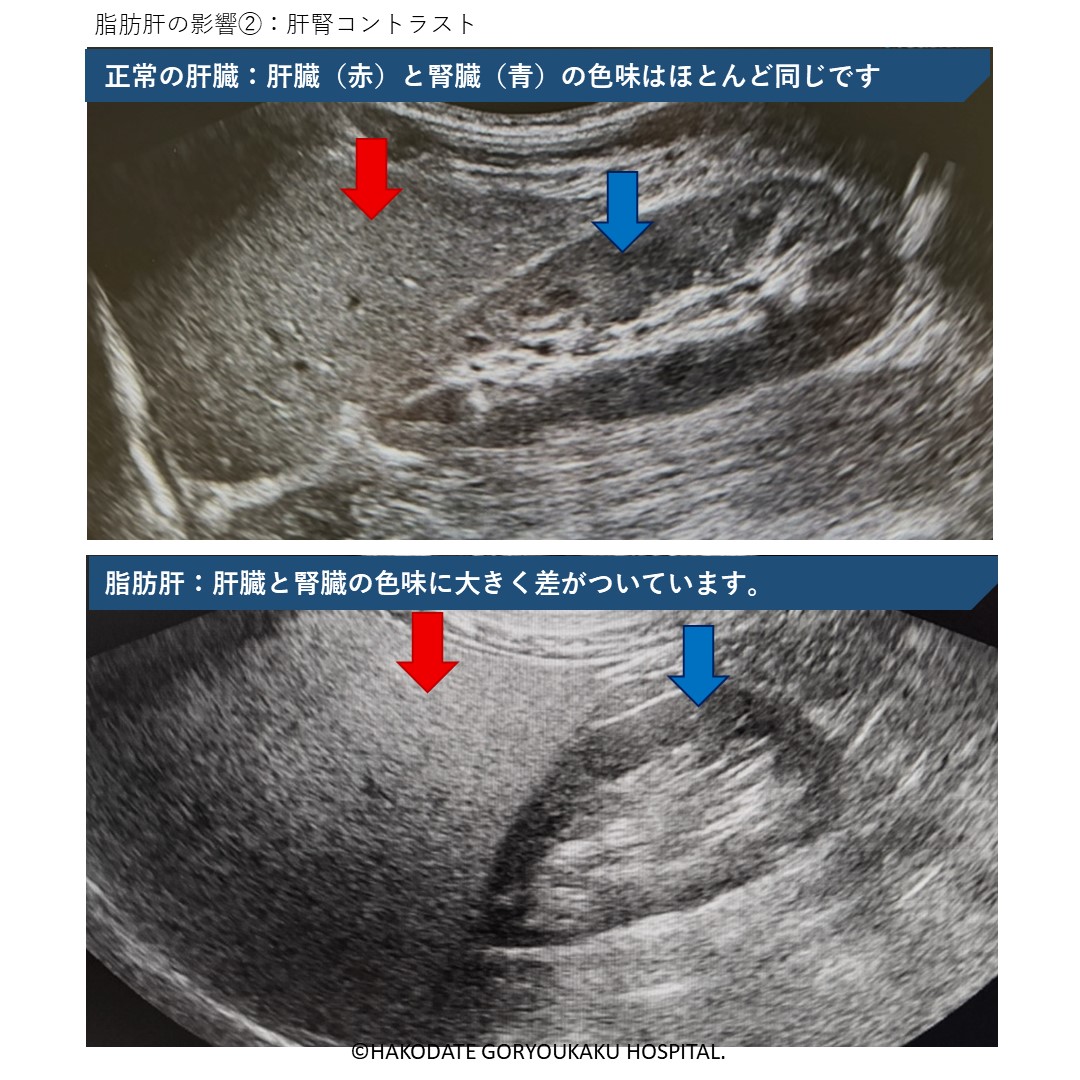

肝腎コントラスト

正常の肝臓であれば、肝臓の色と腎臓の黒い部分の色味はほとんど同じになります。肝臓に脂肪が沈着するほど、肝臓が白っぽくなり、肝臓と腎臓の色味の差が大きくなります。